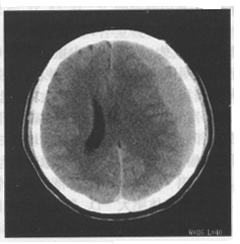

患者男,24岁。头部被球击中,1周后出现持续性头痛、头晕,结合CT图像,最可能的诊断是 YZ463_138_1.gif

• A.硬膜外血肿

• B.脑挫裂伤

• C.急性硬膜下血肿

• D.亚急性硬膜下血肿

• E.慢性硬膜下血肿